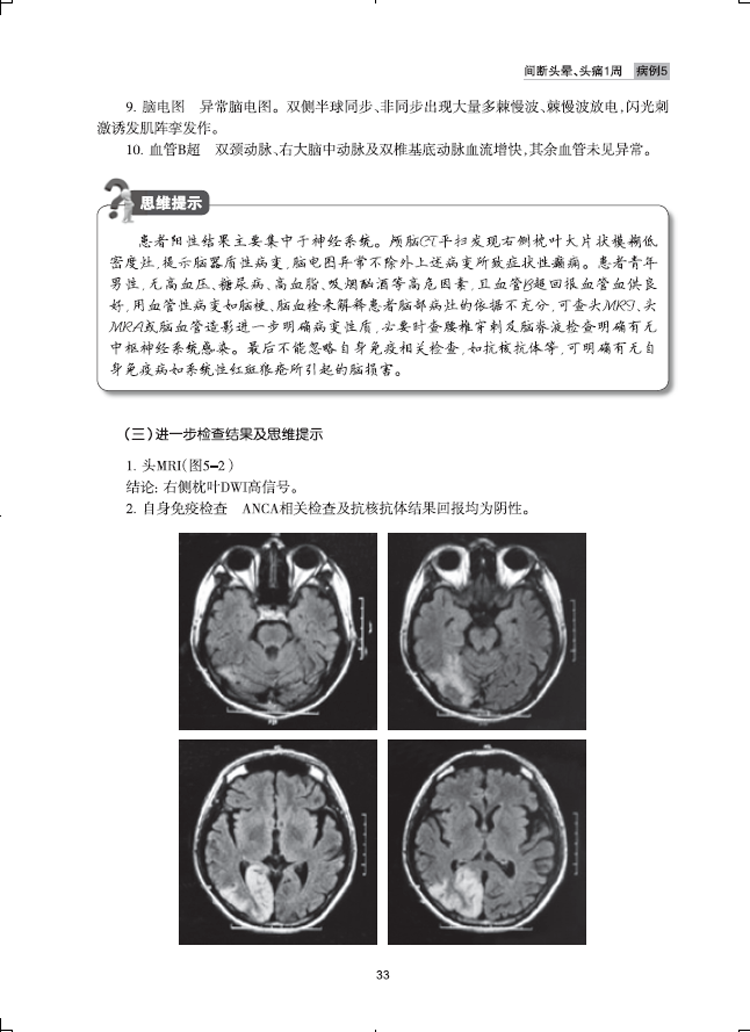

病例5  间断头晕、头痛1周